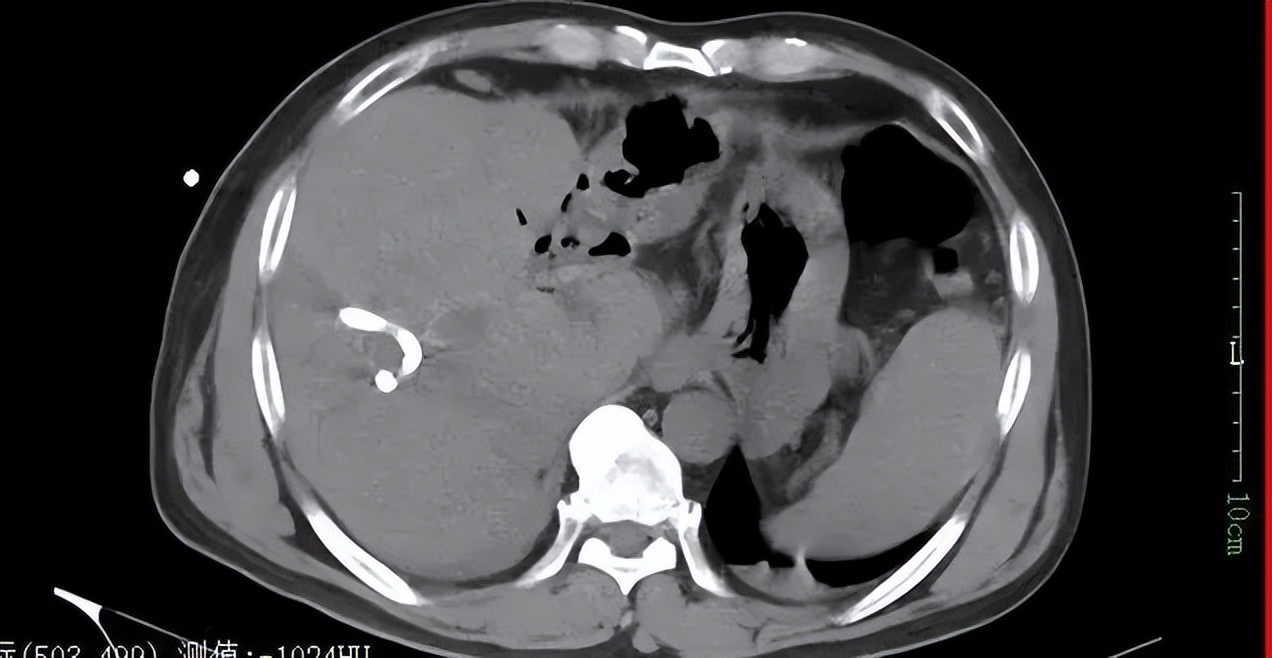

▲术后CT